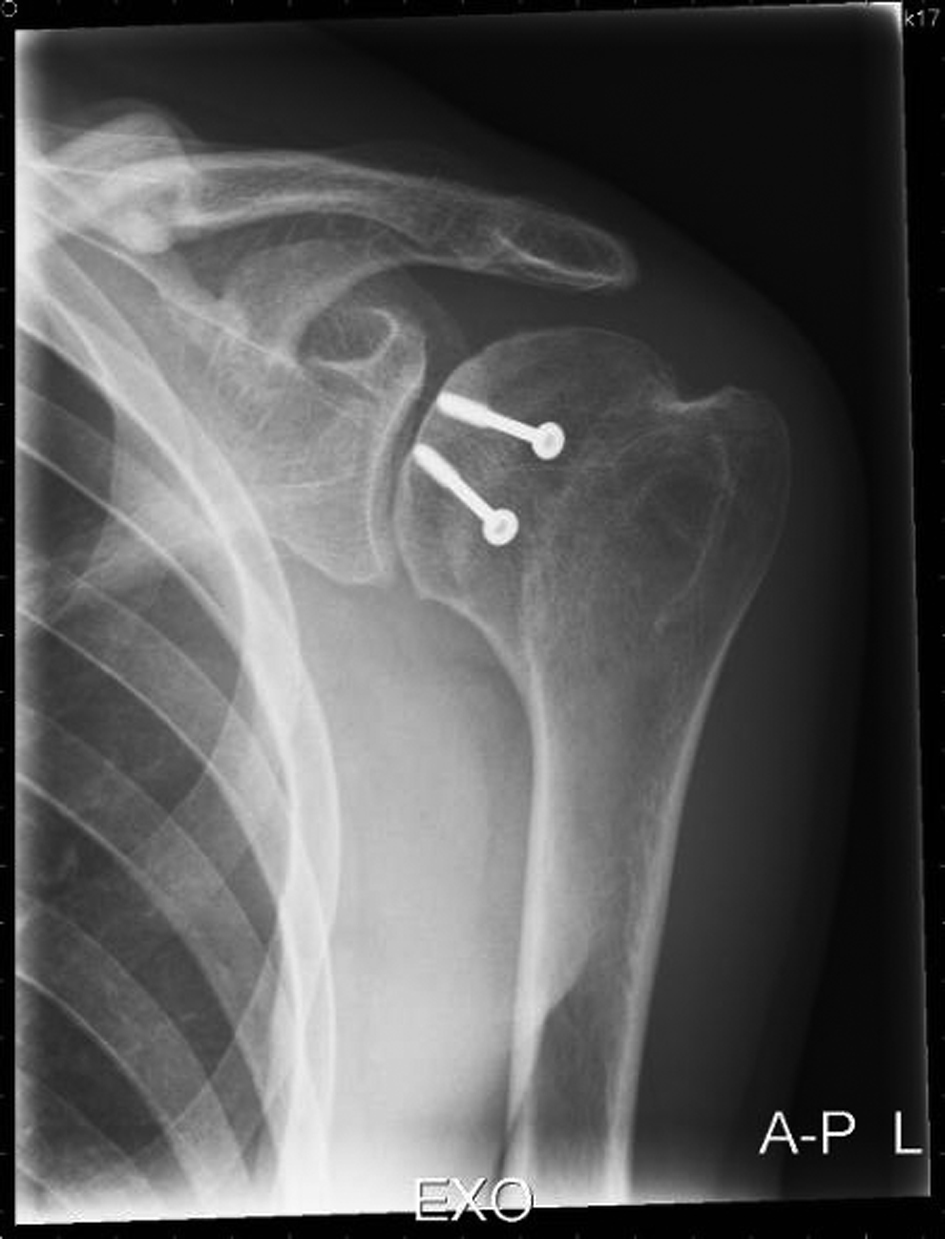

(A) Reverse Hill-Sachs lesion. (B) Post-op X-ray of Neer ...

(A) Reverse Hill-Sachs lesion. (B) Post-op X-ray of Neer ... from www.researchgate.net